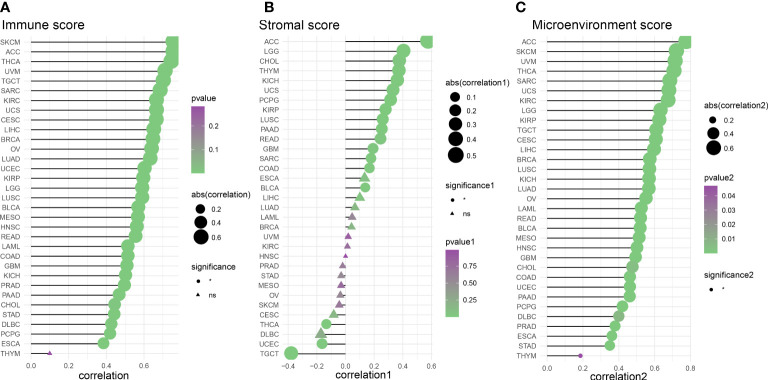

We evaluated 33 different types of tumors for determining associations between IFN-γ score and discovered a positive link between IFN-γ and M1 and M2 Macrophages, T cells follicular helper cells, activated NK cells, and CD8 T cells in most cancers. Also, the IFN-γ score showed an inverse association with T cell CD4 naïve and NK cell resting. (f9). In the analysis of tumor immune score, the IFN-γ score was found to have a positive correlation with the degree of immune cell infiltration in most of the 33 tumors studied (P < 0. 05, f10, Supplementary Figure 7). For PCPG, LUSC, PAAD, SARC, READ, KIRP, COAD, GBM, UCS, KICH, THYM, CHOL, LGG, and ACC, IFN-γ score was positively linked to stromal cell score (f10). Additionally, the IFN-γ score had a positive link to the TME score of ACC, SKCM, UVM, THCA, SARC, UCS, KIRC, LGG, KIRP, TGCT, CESC, LIHC, BRCA, LUSC, KICH, LUAD, OV, LAML, READ, BLCA, MESO, HNSC, GBM, CHOL, COAD, UCEC, PAAD, PCPG, DLBC, PRAD, ESCA, STAD, and THYM (All P < 0. 05, f10). The above results indicate that IFN-γ is closely related to the immune status of tumors.